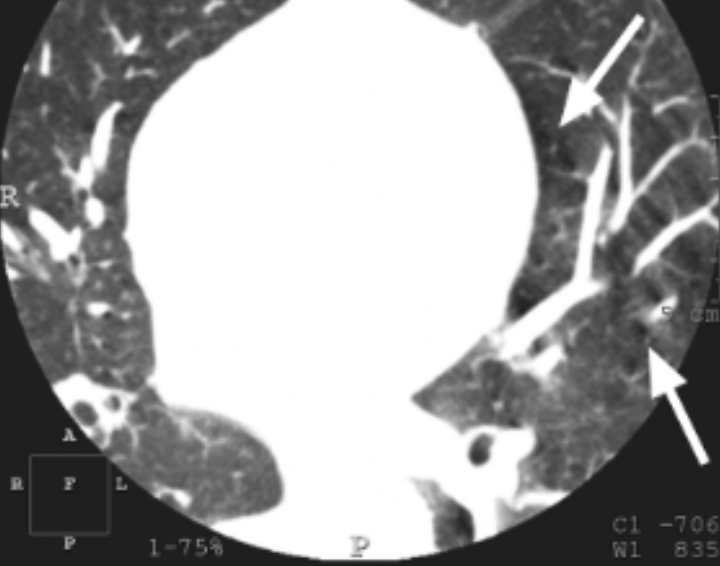

What is the arrow pointing at?

RV pacemaker leads - metal artifacts

Artifacts from dual chamber pacemaker leads MOST likely affect the image quality of the:

RCA